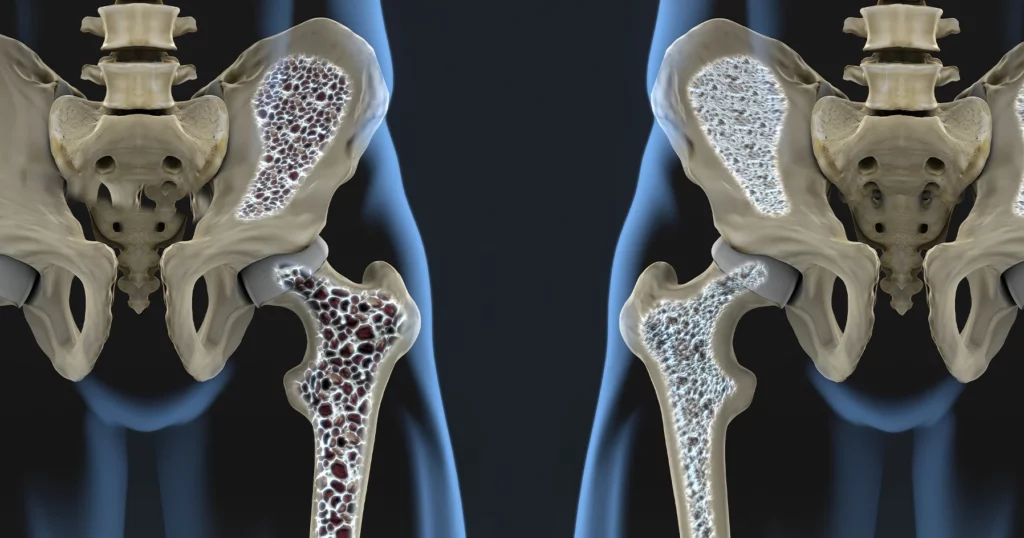

O echipă de cercetători din Germania anunță o descoperire revoluționară în tratamentul osteoporozei, o boală care afectează milioane de oameni la nivel mondial. Un receptor celular, puțin cunoscut până acum, s-ar putea dovedi cheia pentru refacerea densității osoase și oprirea fragilizării oaselor. Experimentele pe animale au arătat rezultate promițătoare, deschizând calea pentru noi abordări terapeutice.

Conform rezultatelor preliminare, receptorul GPR133, identificat de specialiștii din LEIPZIG, joacă un rol crucial în controlul rezistenței osoase. Prin activarea acestuia, cercetătorii au observat o creștere semnificativă a densității osoase și o regenerare a țesutului osos deteriorat în cadrul studiilor pe animale. Această descoperire reprezintă un pas important în înțelegerea mecanismelor moleculare ale osteoporozei și oferă o nouă țintă pentru dezvoltarea de medicamente.

Osteoporoza este o afecțiune caracterizată prin pierderea densității osoase și deteriorarea arhitecturii osoase, ceea ce crește riscul de fracturi. Boala afectează în special persoanele în vârstă și este o problemă majoră de sănătate publică, cu consecințe semnificative asupra calității vieții și costurilor de îngrijire medicală. Tratamentul actual se concentrează, în principal, pe încetinirea progresiei bolii și prevenirea fracturilor, dar nu poate vindeca osteoporoza.